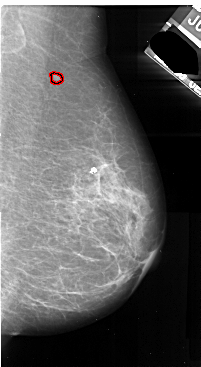

A_1040_1.LEFT_CC

LEFT_CC LINES 5236 PIXELS_PER_LINE 3211 BITS_PER_PIXEL 16 RESOLUTION 42 NON_OVERLAY

FILE: A_1040_1.RIGHT_MLO.OVERLAY

TOTAL_ABNORMALITIES 1

ABNORMALITY 1

LESION_TYPE MASS SHAPE IRREGULAR MARGINS ILL_DEFINED

ASSESSMENT 4

SUBTLETY 1

PATHOLOGY MALIGNANT

TOTAL_OUTLINES 1

BOUNDARY